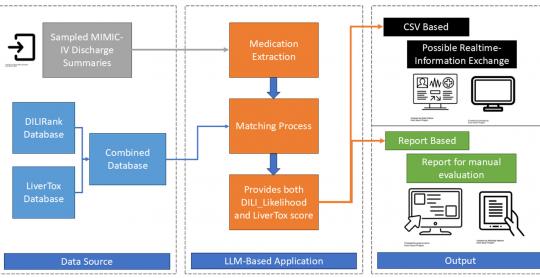

Gastroenterology Research

Vol. 18, No. 5, Oct 2025, pages 247-253

By Thanathip Suenghataiphorn et al.